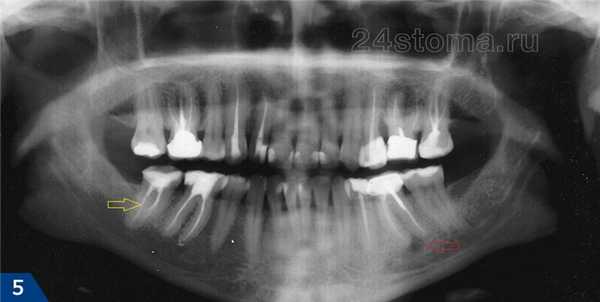

Поэтому четкими будут только однокорневые, а также двухкорневые зубы верхней и нижней челюсти (два корня находятся в одной плоскости) – и причем только на цифровых снимках. А вот передние зубы обоих челюстей на обычных пленочных ортопантомографах будут всегда сильно размыты (рис.5) – в силу сильного изгиба передних отделов челюстей, а также технических несовершенств старого пленочного оборудования.

Например, вполне возможно увидеть положение зубов мудрости, определить качество пломбирования корневых каналов, увидеть воспаление у верхушек корней зубов (гранулемы и кисты, рис.5), рассмотреть снижение уровня костной ткани при пародонтите. Чтобы увидеть, как выглядит соответствующая патология на рентгеновских снимках – перейдите по ссылкам выше и сравните с тем, что вы видите на своем панорамном снимке.